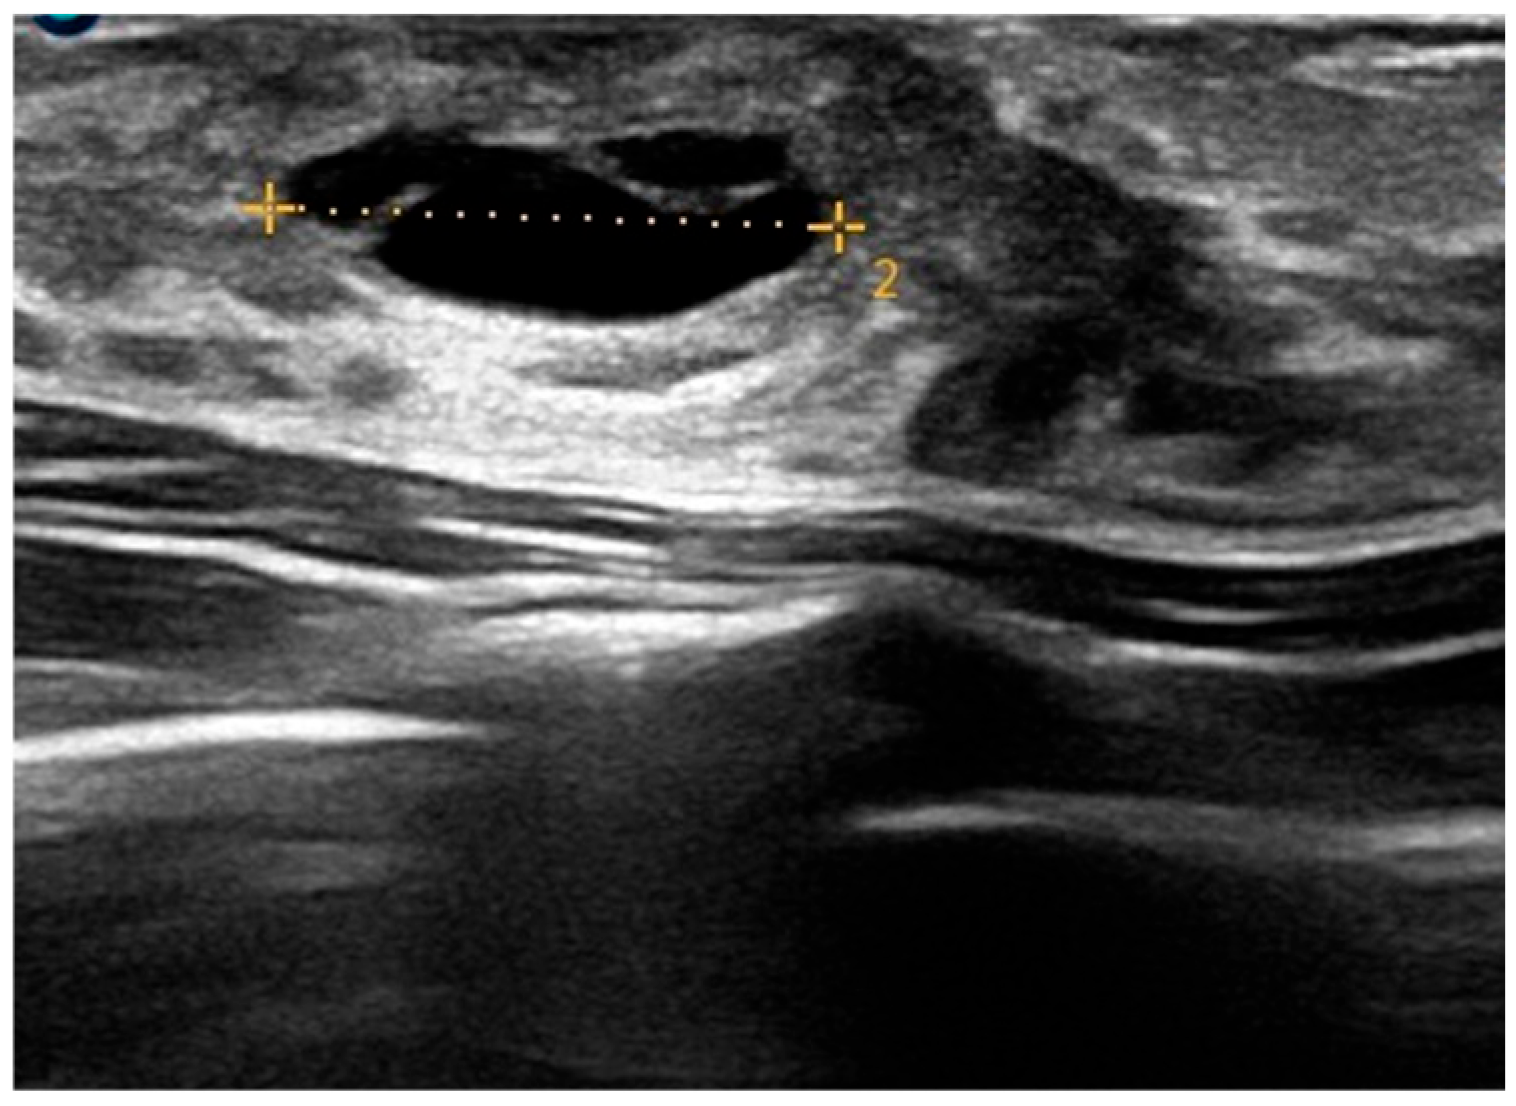

| Retroareolar cysts | Superficial, soft, smooth and bluish lesions | Homogeneous, unstructured greenish discoloration with blurred edges | Anechoic, oval, thin-walled mass with posterior enhancement; no Doppler flow | Prepuberal age |